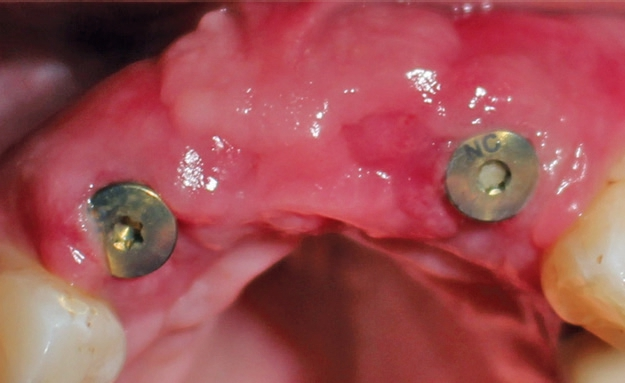

Das post-operative Follow-up zeigte eine komplikationslose Heilung. Sechs Monate nach der Operation wurde das Re-entry durchgeführt und Gingiva-Former eingesetzt (Abb. 19). Die provisorische Brücke zeigte ästhetische Ergebnisse bereits sechs Monate nach Operation (Abb. 20). Das Röntgenbild zeigte stabile Knochenverhältnisse (Abb. 21).